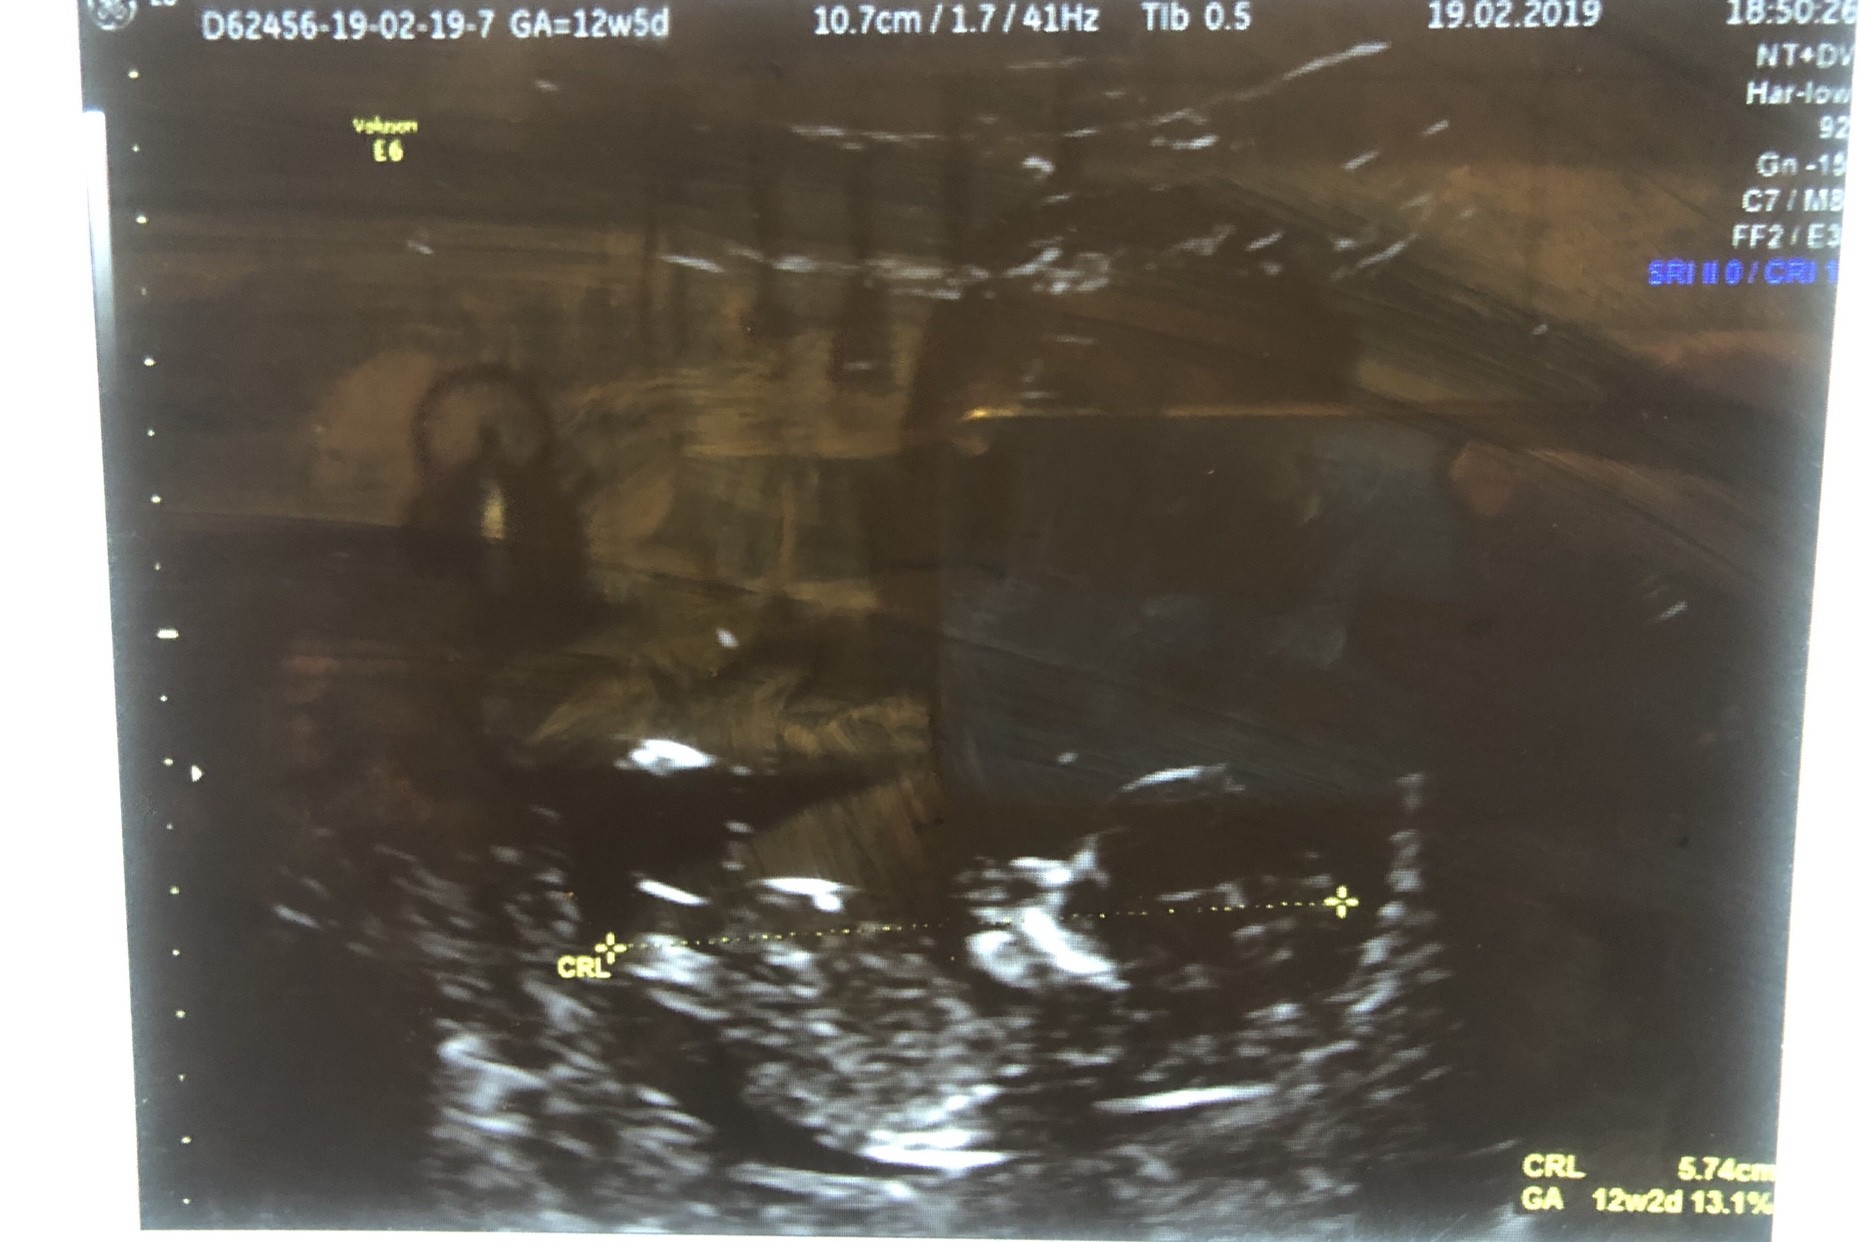

IMG_3300.JPG

Nasze bobo [emoji177]

ale cudny widok jak jest jeszcze maluszek w calosci :)